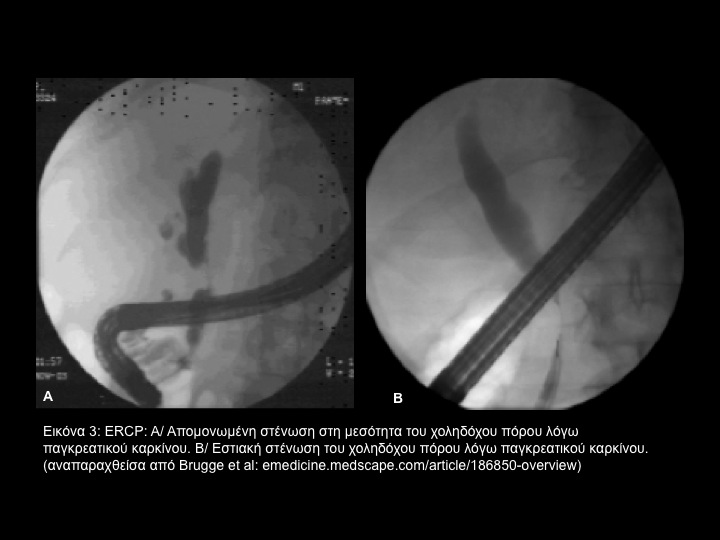

Το παγκρεατικό αδενοκαρκίνωμα είναι η συνηθέστερη αιτία κακοήθους αποφράξεως των χοληφόρων. (Eικόνα 3) Ευθύνεται για 33.000 νέες περιπτώσεις κατ' έτος στις Ηνωμένες Πολιτείες και είναι η 5η συνηθέστερη αιτία θανάτου από καρκίνο. Παρουσιάζεται συνήθως μετά την 6η δεκαετία της ζωής.